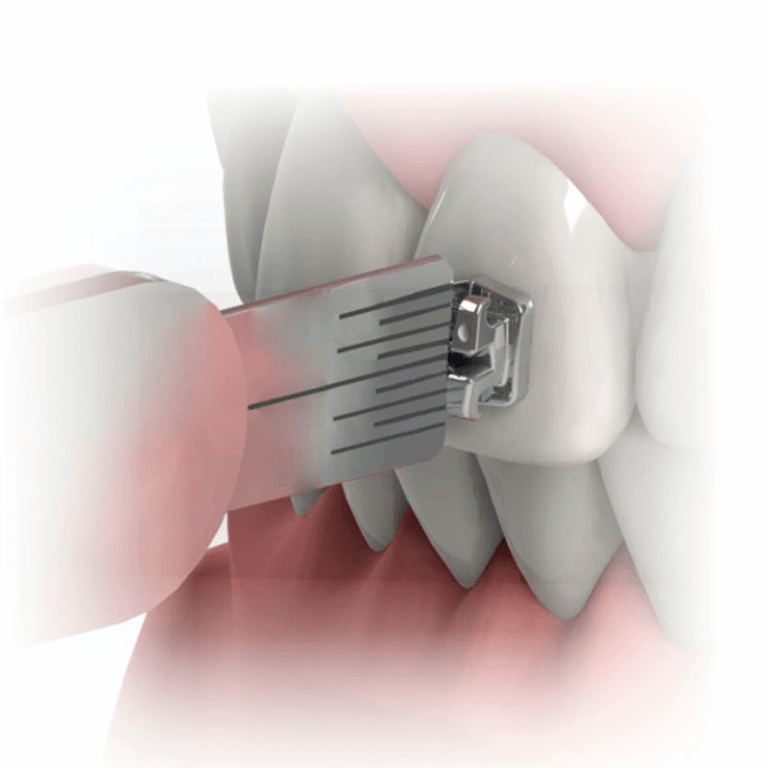

- Bandas Molares

- Tubos Molares